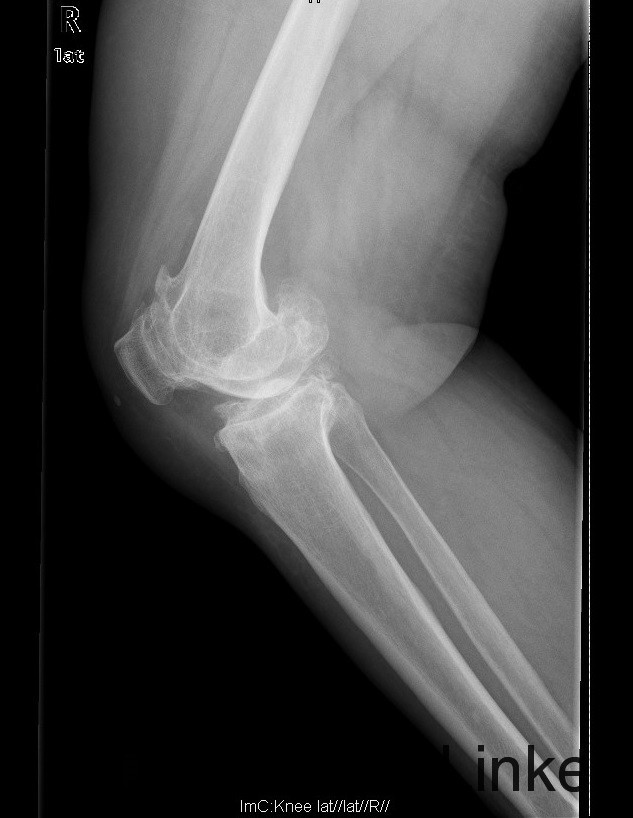

查体:步态跛行,双膝屈曲畸形,左膝外翻、右膝内翻畸形,双膝内外侧关节间隙及髌股关节间隙压痛明显,右侧重,右膝内翻:5°,右膝屈70°,伸-10°;左膝:屈曲:100°,伸:-5°,外翻:20°,双膝主被动屈伸活动时疼痛,双膝髌下摩擦音(+)。 辅助检查:右膝关节间隙狭窄,软骨下骨硬化,髌股关节间隙消失,左膝关节间隙狭窄,软骨下骨硬化,髌股关节间隙狭窄,双膝髌骨、股骨、胫骨周围大量骨赘形成,关节腔内均可见游离体。

诊断:1.双膝重度骨关节炎继发右膝屈曲内翻畸形,左膝屈曲外翻畸形(Krackow Ⅰ型)2.高血压病(3级 极高危) 治疗:积极行术前准备,待血压等稳定后于全麻下行右侧全膝关节置换术,术后常规治疗,并鼓励其锻炼。